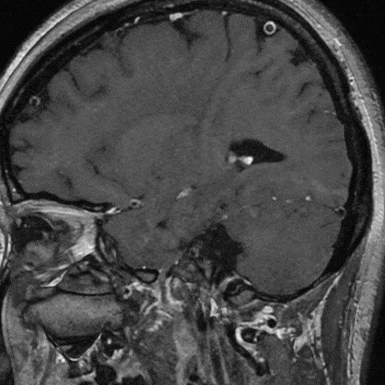

术前影像入院前头颅CTA提示:左侧颈内动脉C7段末端动脉瘤。

入院后查高分辨核磁显示:左侧颈内动脉交通段、左侧大脑前动脉A1段及左侧大脑中动脉M1段管壁明显强化,左侧颈内动脉交通段及左侧大脑中动脉M1段管腔内可见强化内膜片影,考虑左侧颈内动脉交通段夹层动脉瘤累及M1、A1段(左侧颈内动脉交通段及左侧大脑中动脉M1段管腔扩张,左侧大脑前动脉A1管腔明显狭窄)。